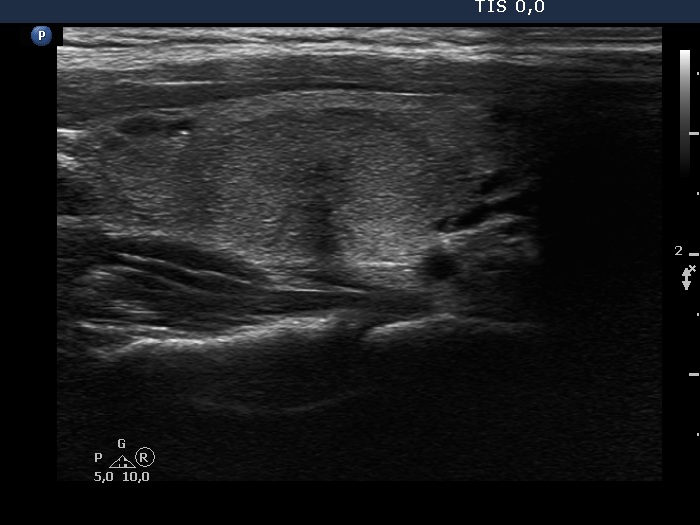

Right lobe, longitudinal scan

Right lobe, longitudinal scan. There is another, smaller nodule in the upper part of the lobe.